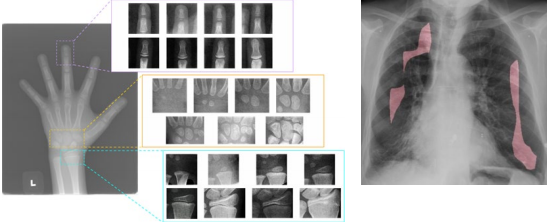

의료 영상 처리

- X-ray 또는 CT 영상 처리

- 영상의 화질 개선, 영상의 자동 분석